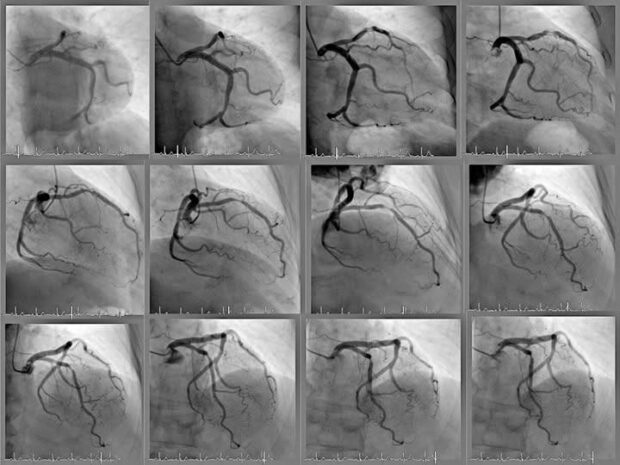

Señaló que el trabajo se centró en el análisis automatizado de imágenes médicas internas del corazón, específicamente angiogramas, con el objetivo de identificar zonas de estrechamiento entre arterias que puedan derivar en infartos o paros cardíacos.

La investigación utilizó un conjunto de datos denominado ARCADE, generado en 2022 para un concurso internacional orientado al diagnóstico de problemas del corazón. A partir de esta base, se entrenaron modelos de aprendizaje profundo mediante la técnica YOLO (You Only Look Once), lo cual permitió segmentar imágenes en escala de grises para detectar con precisión tanto los vasos sanguíneos como las zonas críticas de estenosis.